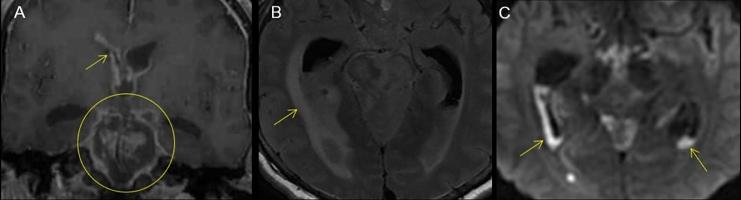

Rupture of brain abscesses with evolution into ventriculitis with meningitis may result in sudden and dramatic worsening of the clinical situation. We present a 57-year-old man with such an event and fatal outcome. Multiple imaging modalities including computed tomography and advanced magnetic resonance imaging were correlated with gross specimen and histologic images. The differential diagnosis of multiple lesions with ring enhancement and prominent perifocal edema includes mainly infectious and neoplastic processes, such as brain abscess, metastasis, and multicentric glioblastoma. Pyogenic ventriculitis is an uncommon manifestation of severe intracranial infection that might be clinically obscure. We discuss the characteristic magnetic resonance findings of brain abscess and its complications, including meningitis and ventriculitis with emphasis on the role of diffusion-weighted and fluid-attenuated inversion recovery imaging.

脑脓肿破裂并演变为脑室炎合并脑膜炎可能导致临床状况突然急剧恶化。我们报告一名57岁男性发生了这样的事件并导致了致命后果。包括计算机断层扫描和先进磁共振成像在内的多种成像方式与大体标本及组织学图像相关联。具有环形强化和明显灶周水肿的多个病变的鉴别诊断主要包括感染性和肿瘤性病变,如脑脓肿、转移瘤和多中心胶质母细胞瘤。化脓性脑室炎是严重颅内感染的一种不常见表现,在临床上可能难以明确诊断。我们讨论脑脓肿及其并发症(包括脑膜炎和脑室炎)的特征性磁共振表现,重点强调扩散加权成像和液体衰减反转恢复成像的作用。